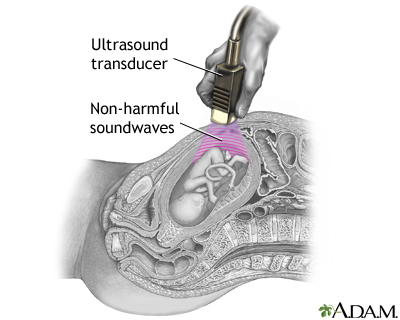

Procedure, part 2

The transducer emits inaudible sound waves, which fan out as they travel through your abdomen. When they hit dense structures like the fetus and the wall of your uterus, the sound waves bounce back to the transducer and are translated into a visual image by the computer.